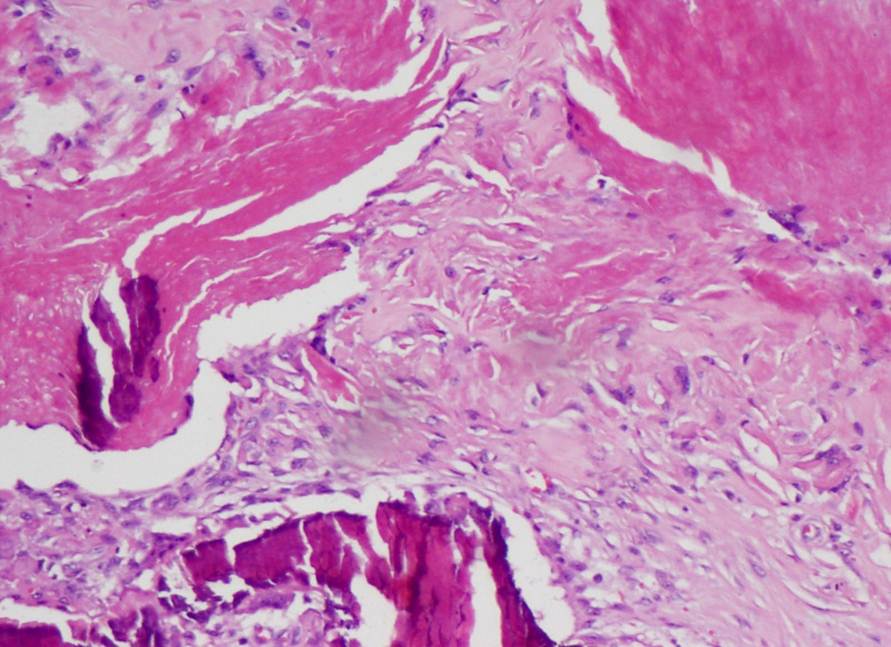

Fig 3,4: Photomicrograph showing islands of shadow cells, with foci of calcification surrounded by basaloid cells (H&E, 200X).